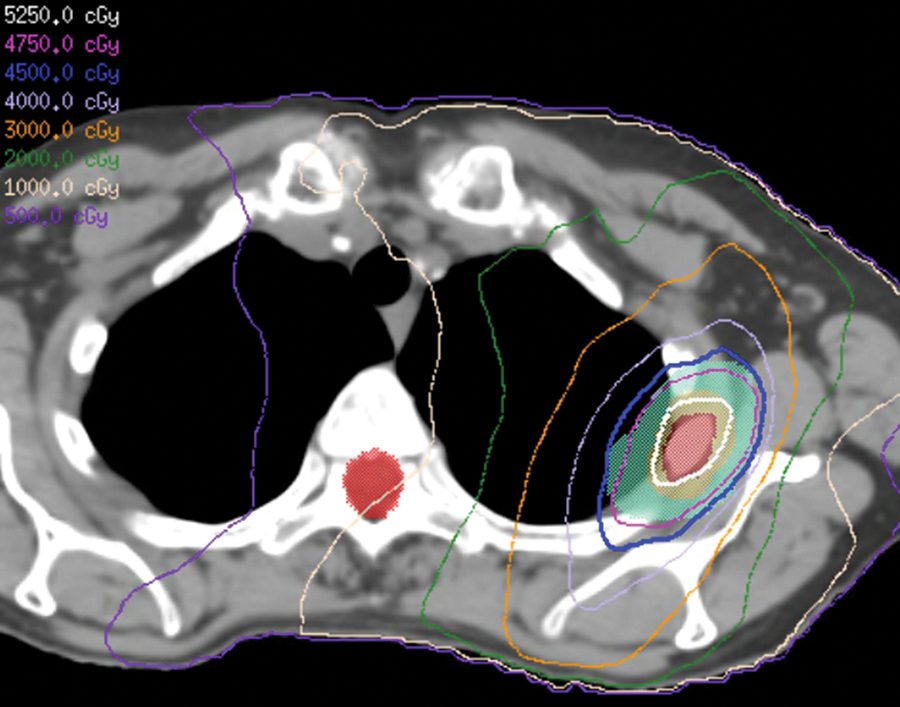

Irradiación hipofraccionada de mama parcial

Ensayo clínico prueba régimen de radioterapia de haz externo durante 10 días después de tumorectomía para pacientes con cáncer de mama de estadio inicial